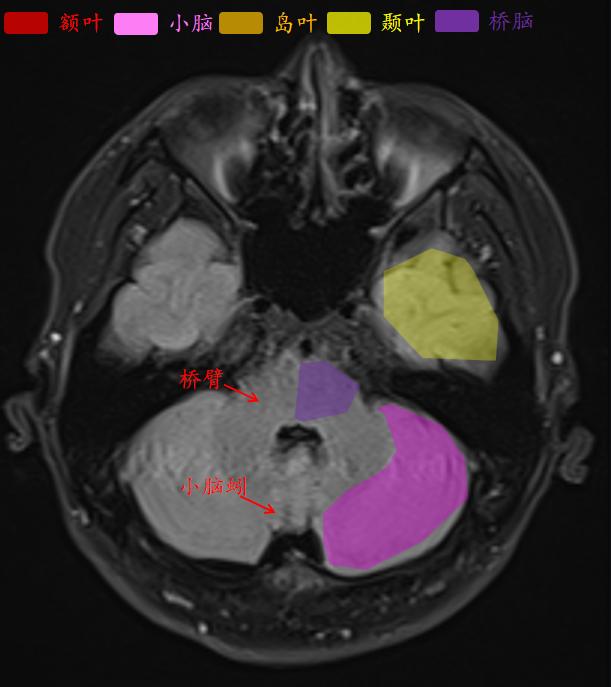

这就是常规医院扫描的t2-flair的相似层厚层间距的图像。

人脑分为:大脑(又称端脑),间脑(背侧丘脑、后丘脑、上丘脑、下丘脑、低丘脑)、小脑和脑干(中脑、脑桥、延髓)。